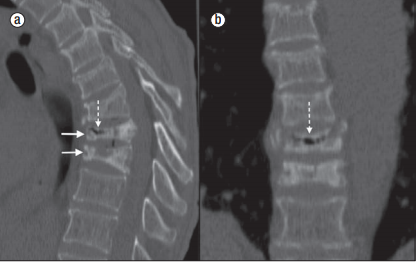

Болезнь Кюммеля-Вернея (болезнь Кюммеля) — это редкое, но достаточно грозное заболевание. Оно подразумевает под собой сосудистый некроз внутрипозвонковых артерий, приводящих к некрозу самих позвонков. Как правило, поражаются тела грудных или поясничных позвонков у людей, пострадавших от компрессионной деформации. Развивается некроз в течении нескольких месяцев после травмы[1,2].

Первая стадия возникает после травмы. Часто наблюдается у лиц тяжелого физического труда и характеризуется мгновенной сильной болью, которая в дальнейшем продолжается в течении нескольких дней, постепенно стихая. Тут начинается вторая стадия, характеризующаяся полным отсутствием жалоб от пациента[4]. Длиться она может от 1–2 месяцев до 8–9[3]. Это усредненные цифры. Третья стадия наступает после вновь приложенного физического воздействия в той же области. Это может быть либо чрезмерная нагрузка, либо просто неудачный поворот тела, либо вновь возникшая травма. Характеризуется она менее интенсивными болями, но все же сходными с теми, что были в первой стадии, как по характеру, так и по локализации. При обследовании пациента может отмечаться ограничение функции, боли при надавливании или поколачивании на выступающий остистый отросток пораженного позвонка, а также, что очень важно, прогрессирующий кифоз[3,4].